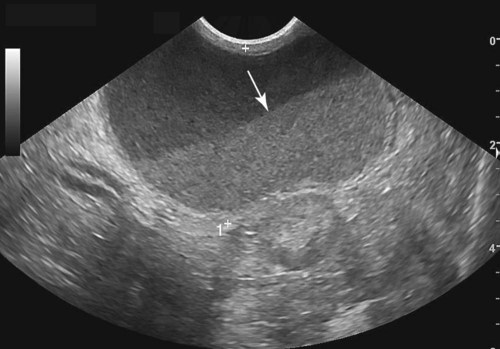

- Ultrason: Pelvik ultrason, rahim içinde sıvı birikimini tespit etmenin en yaygın yöntemlerinden biridir. Bu yöntemle rahimdeki anormal sıvı miktarı ve olası nedenler belirlenir.